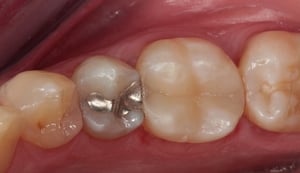

Otturazione in composito a livello di primo molare inferiore destro. Il restauro in amalgama di argento esistente presenta una frattura e viene pertanto sostituito. La rimozione del materiale metallico viene eseguita isolando il dente dal cavo orale mediante diga di gomma. Il dente viene come per ogni procedura sabbiato, mordenzato, trattato con primer ed adesivi ed infine otturato in materiale composito fotopolimerizzabile. La presenza di cuspidi intatte e di spessore sufficiente, conferisce una adeguata resistenza meccanica al restauro eseguito.